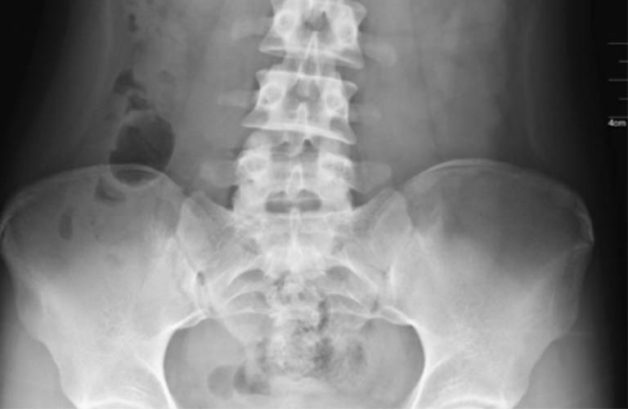

- Kiểm tra hình ảnh: Chụp X – quang, chụp CT hoặc chụp cộng hưởng từ MRI có thế được chi định nếu bác sĩ nghi ngờ các chấn thương dẫn đến viêm khớp cùng chậu. Ngoài ra, xét nghiệm hình ảnh cũng được thực hiện để xác định những thay đổi bên trong khớp xương cùng.